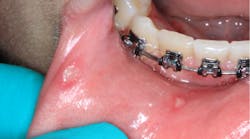

A healthy 16-year-old male presented with this chief complaint: I got my wisdom teeth out five days ago, and I can’t eat or swallow; it hurts. I have bumps all over in my mouth.

Clinical assessment revealed multiple white lesions with red borders salt-and-peppered in a generalized fashion throughout the entire oral cavity. The gum tissues were swollen and any light palpation/touching of the lesions resulted in bleeding and pain. See clinical photos below.

Acute herpetic gingivostomatitis